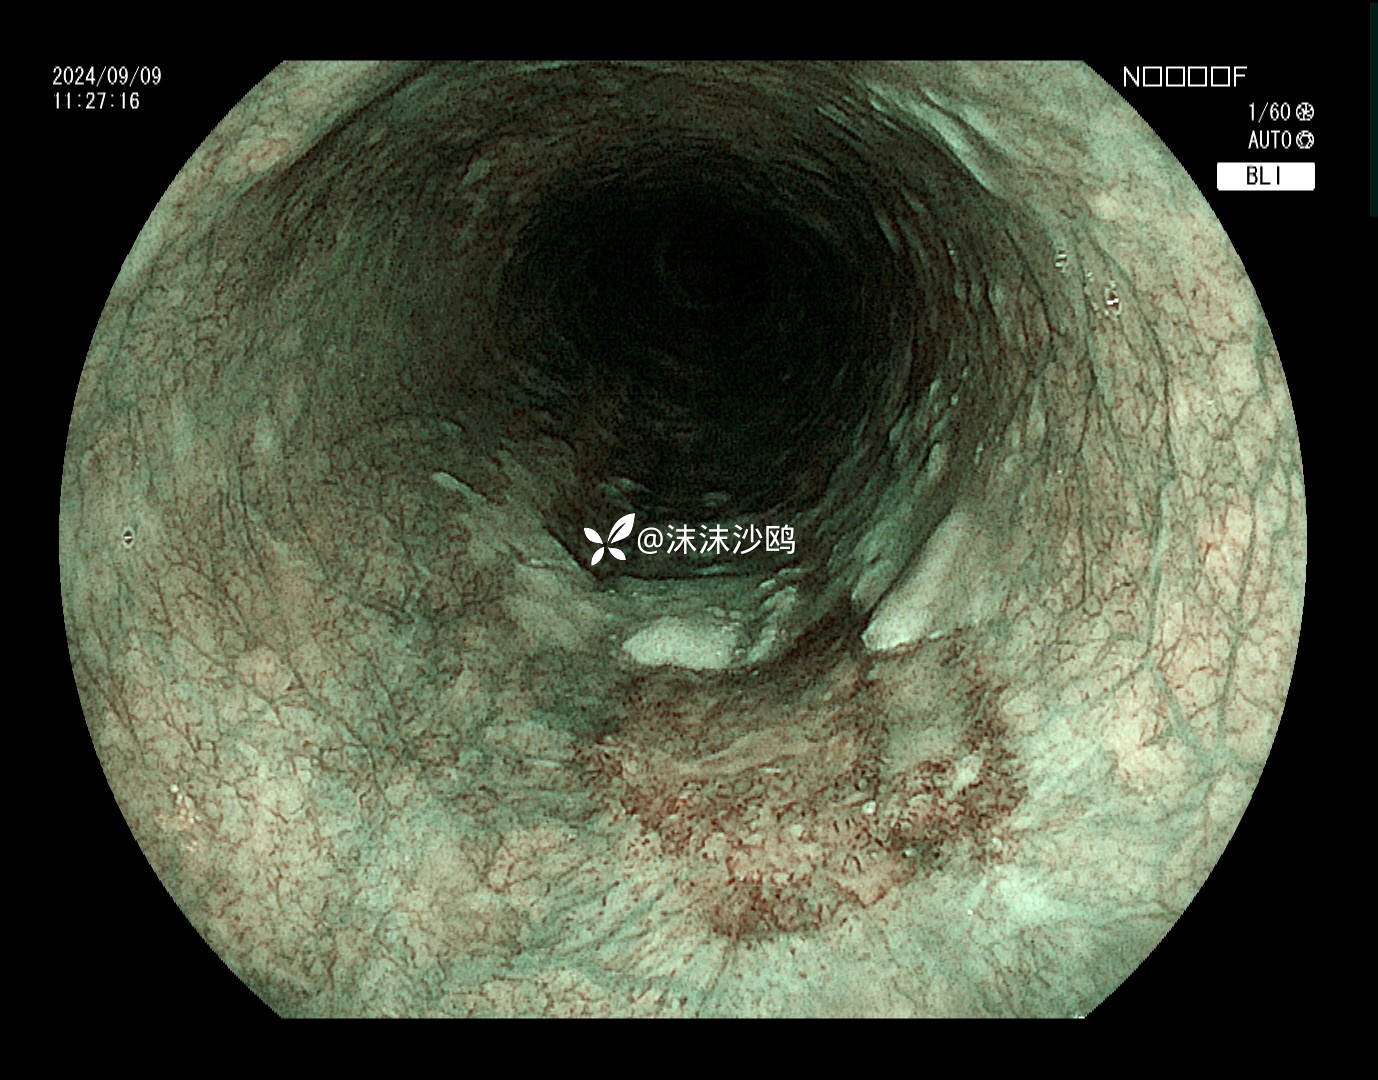

老年男性,腹胀不适门诊行普通胃镜检查。距门齿30cm见片状粘膜粗糙发红,呈0-II b型病灶。

距门齿30cm见片状粘膜粗糙发红,大小约2cm,形态0-II b型

BLI